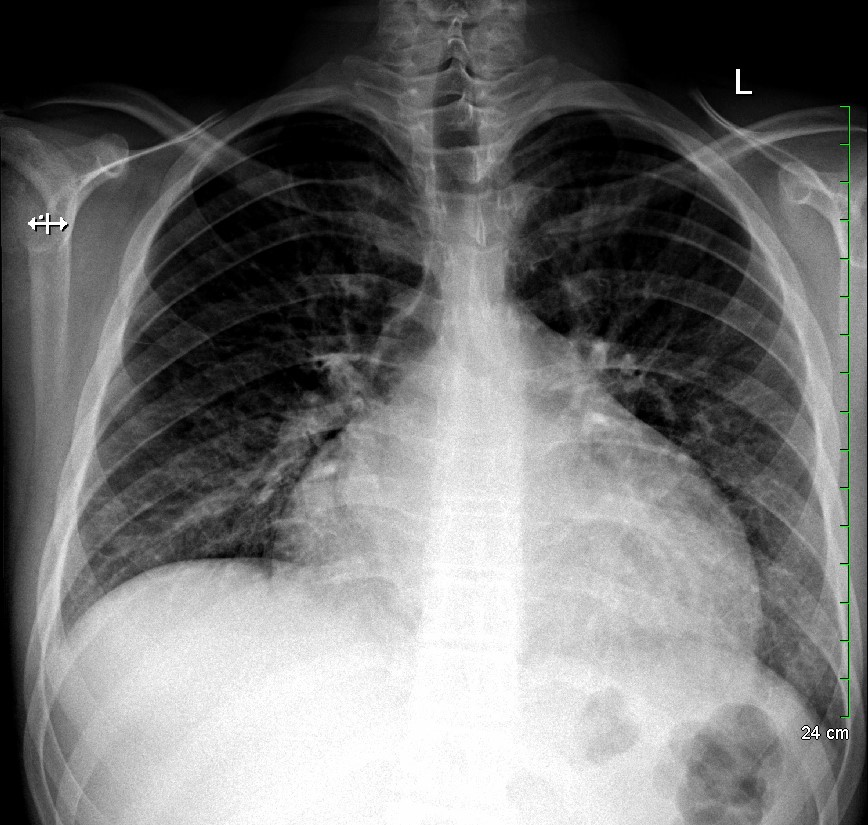

KUB read as normal by radiology. However, because of the enlarged heart border found incidentally on KUB, troponin I (0.05 ng/mL), B-type natriuretic peptide (BNP) (2186 pg/mL), and chest x-ray (CXR) was obtained, which showed the following:

With cardiomegaly confirmed, it was determined that the patient was in heart failure, and that his symptoms of abdominal pain and vomiting were likely the result of abdominal insufficiency. Cardiology performed an echocardiogram, which showed dilated cardiomyopathy, severely reduced systolic function, and a left ventricular ejection fraction of 10-15%. The patient was transferred to a cardiac surgical center for heart transplant.